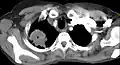

Um tumor de Pancoast é um tumor do ápice pulmonar, ou seja, um tipo de câncer de pulmão definido principalmente pela sua localização situada no topo do pulmão esquerdo ou direito. É tipicamente associado a um histórico de tabagismo.

O crescimento tumoral pode conduzir à compressão da veia braquiocefálica, artéria subclávia , nervo frénico, nervo laríngeo recorrente, nervo vago, ou caracteristicamente a compressão da cadeia simpática cervical, e concomitantemente o desenvolvimento da síndrome de Horner.